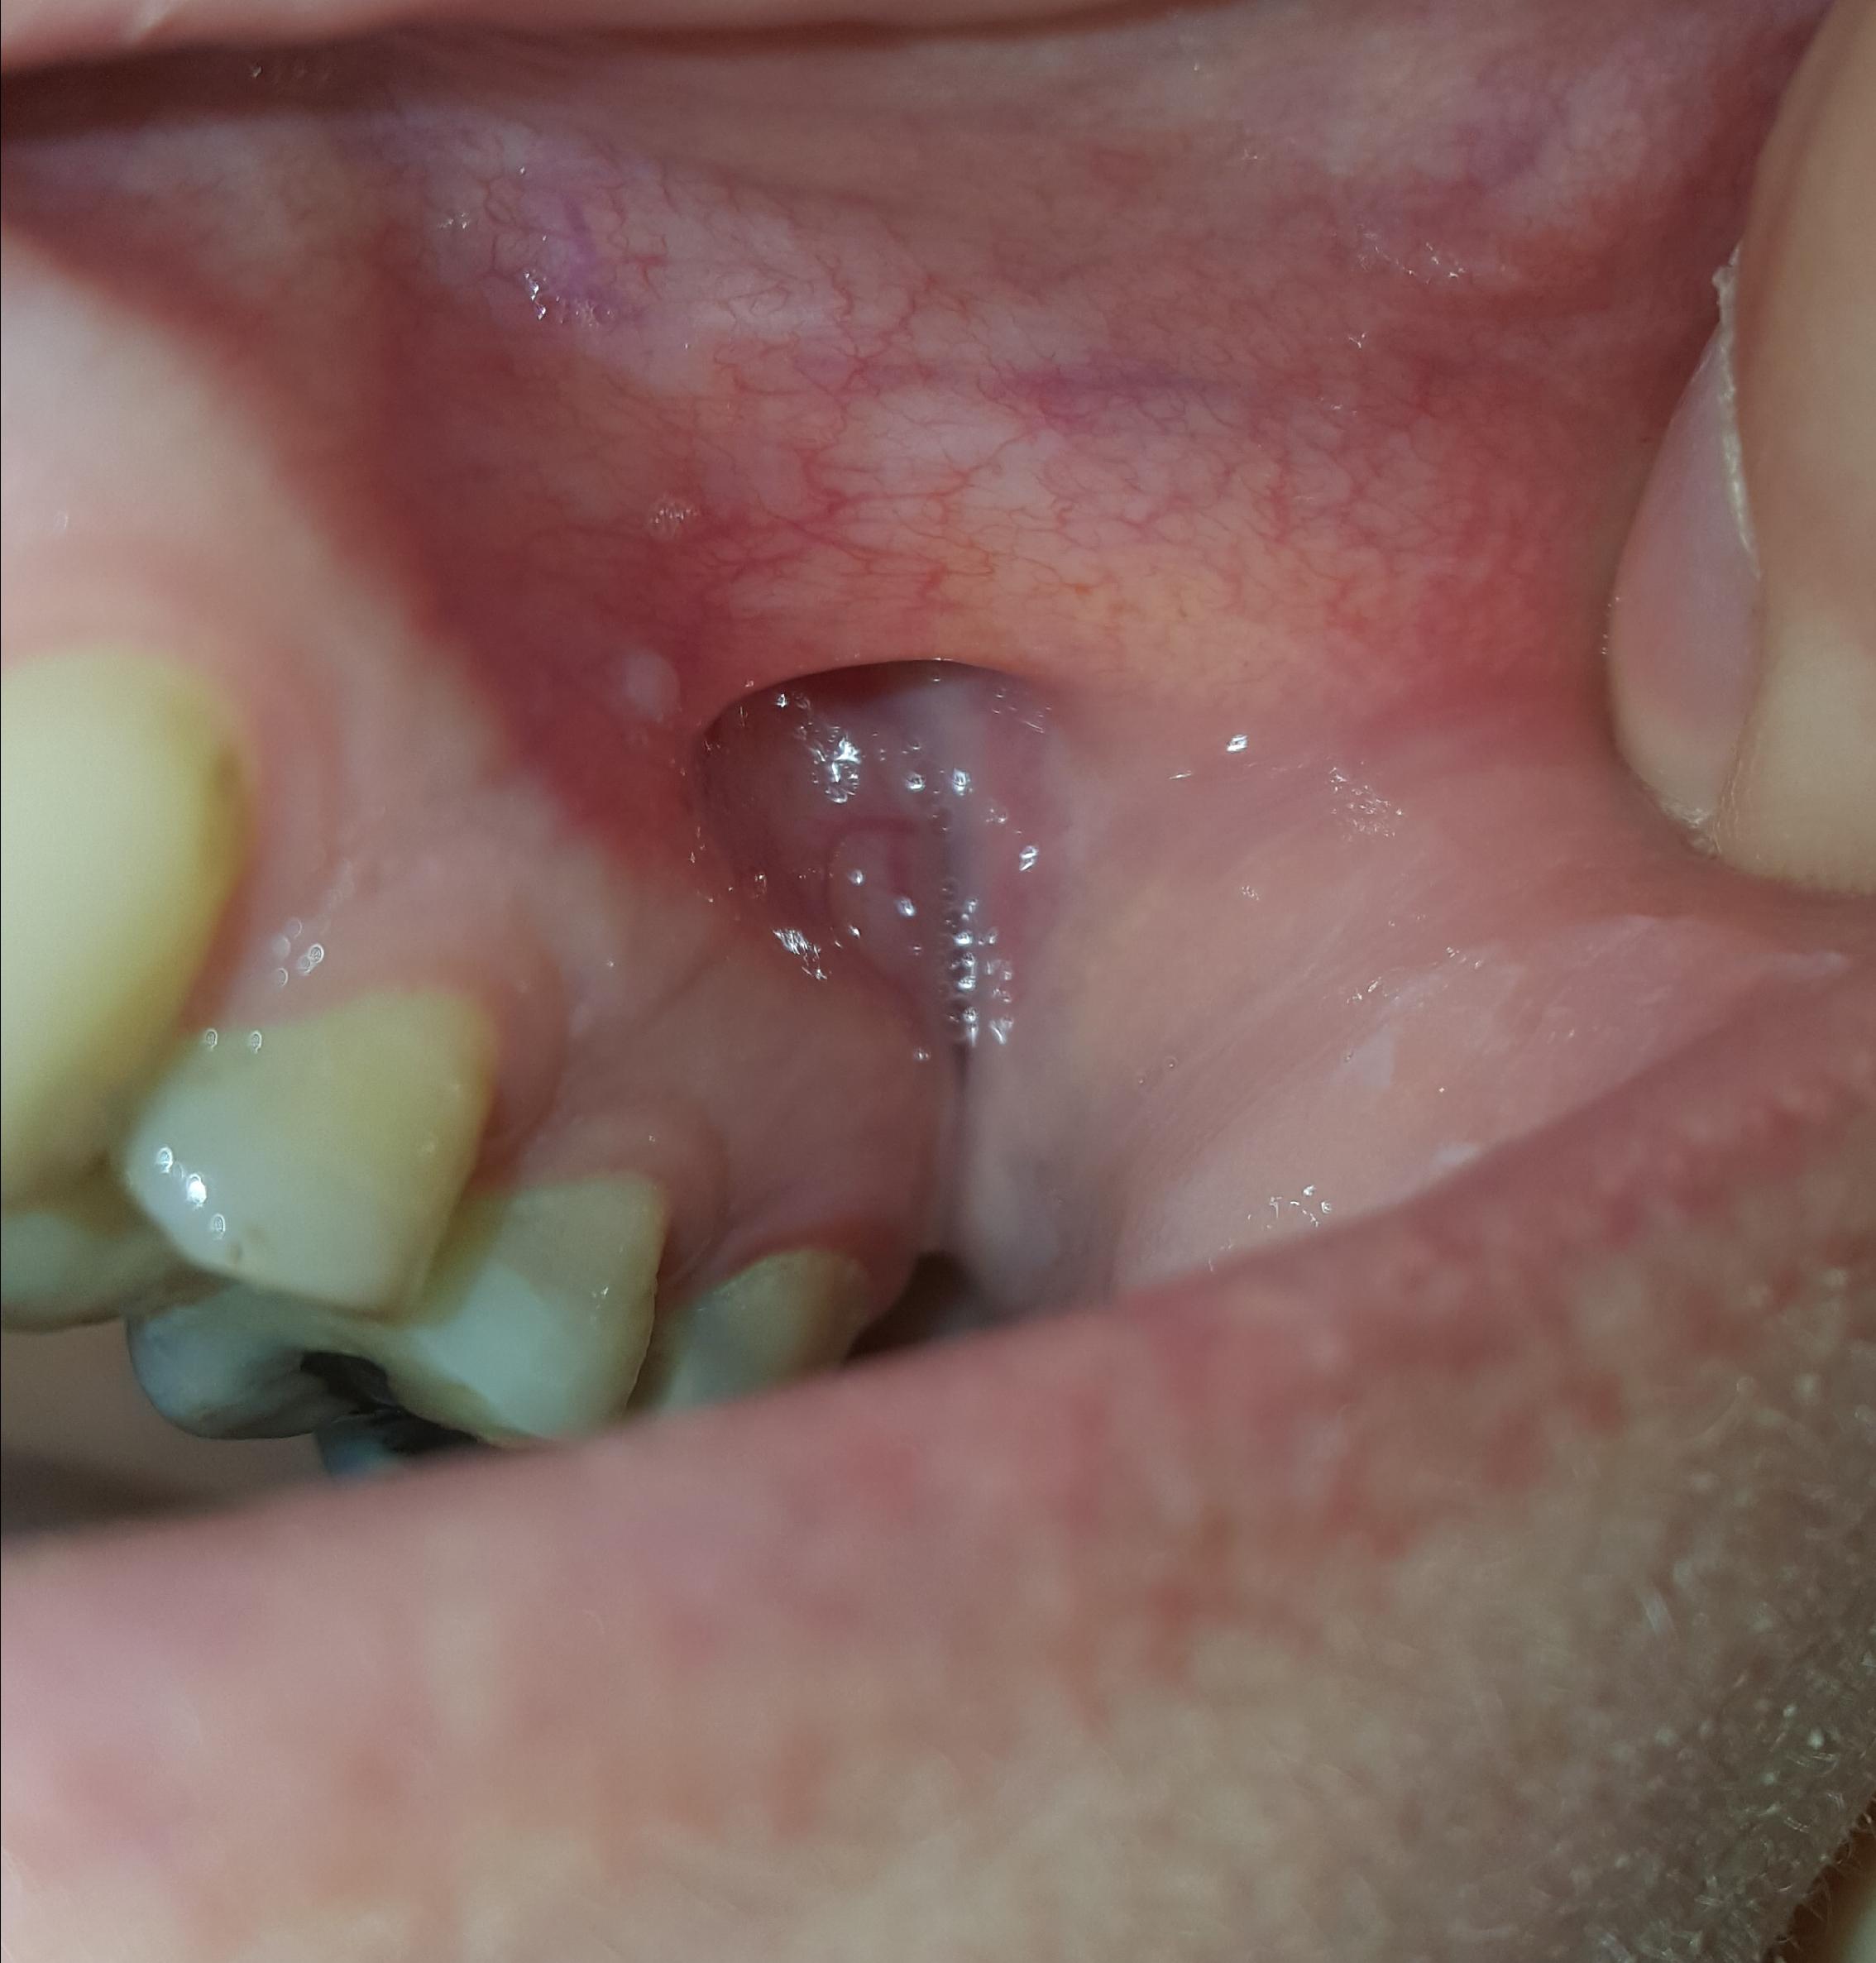

Zie bultje in de mond. Is dit een fistel?

Ik heb verder geen klachten en pijn. Er komt ook niks uit.

Het zit vrij hoog.

Foto 1 is van vandaag, Foto 2 van gisteren.